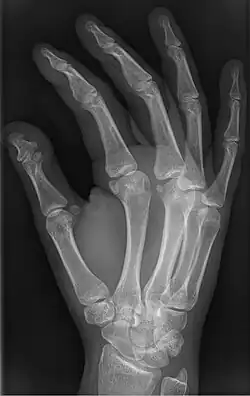

Brachyphalangy of the thumb's distal phalanx, also known as brachydactyly type D, with otherwise normal phalanges of the 2nd-5th digits

Brachyphalangy of the distal phalange of the thumb

This condition is caused by either fusion or early closure of the phalange's growth plate. One example is brachydactyly type D, which is caused by an early closure of the thumb's distal phalange, leading to a congenitally short thumb with a similarly short and wide thumb nail.